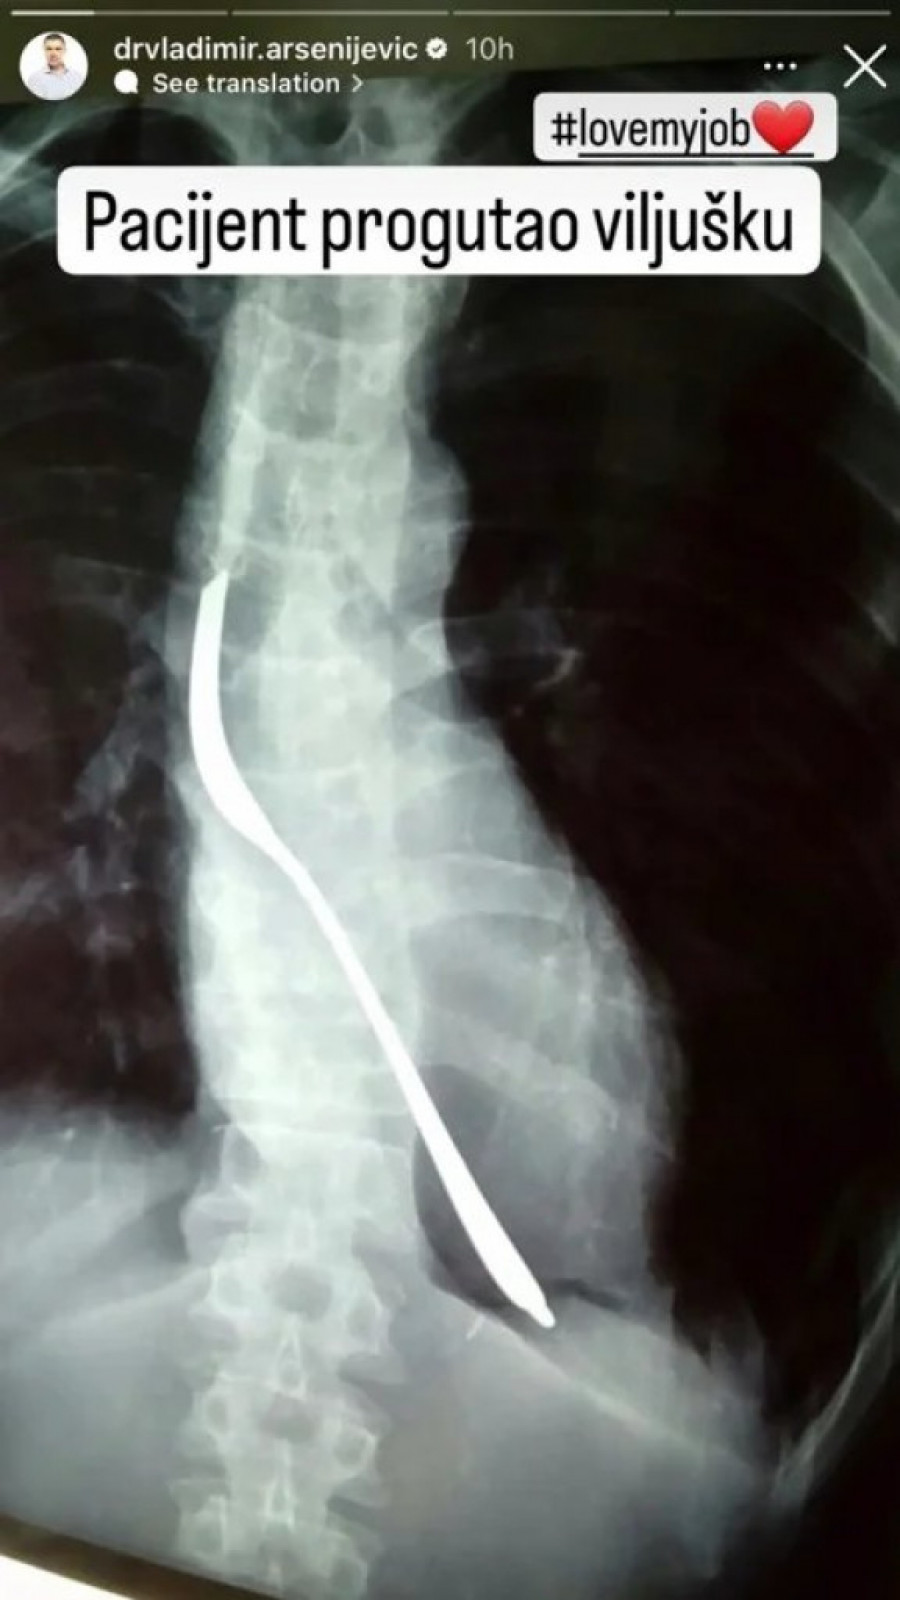

BEOGRAĐANIN POJEO VILJUŠKU! Neviđen slučaj u URGENTNOM CENTRU, lekari šokirani prizorom!

Užas i neverica zavladali su Urgentnim centrom u Beogradu kada je jedan pacijent dospeo u ordinaciju sa neobičnim problemom - progutao je viljušku!

Detalji o pacijentu ostaju nepoznati, ali se pretpostavlja da će se viljuška morati ukloniti operativnim putem. Stalno smo svedoci slučajeva kada deca progutaju sitnije predmete, ali ovakav incident nije viđen godinama.